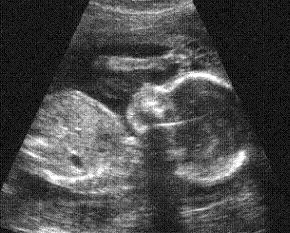

Ultrasound technology and laws credited for pro-life shift

Some doctors and pro-life leaders now say ultrasound technology is partly responsible for Americans' gradual shift to identifying themselves as pro-life. Nebraskan legislators are now considering joining the many states which require that a woman considering an abortion be provided an ultrasound of her baby.

"Ultrasound used to be less available, very grainy. Now the baby is very clear, very distinct," Charmaine Yoest of Americans United for Life told Fox News.

Massachusetts Doctor Eric J. Keroack reported to Fox News that a two-year study showed 75 percent of his patients who were unsure about having an abortion decided not to after choosing to view the ultrasound images of their child.